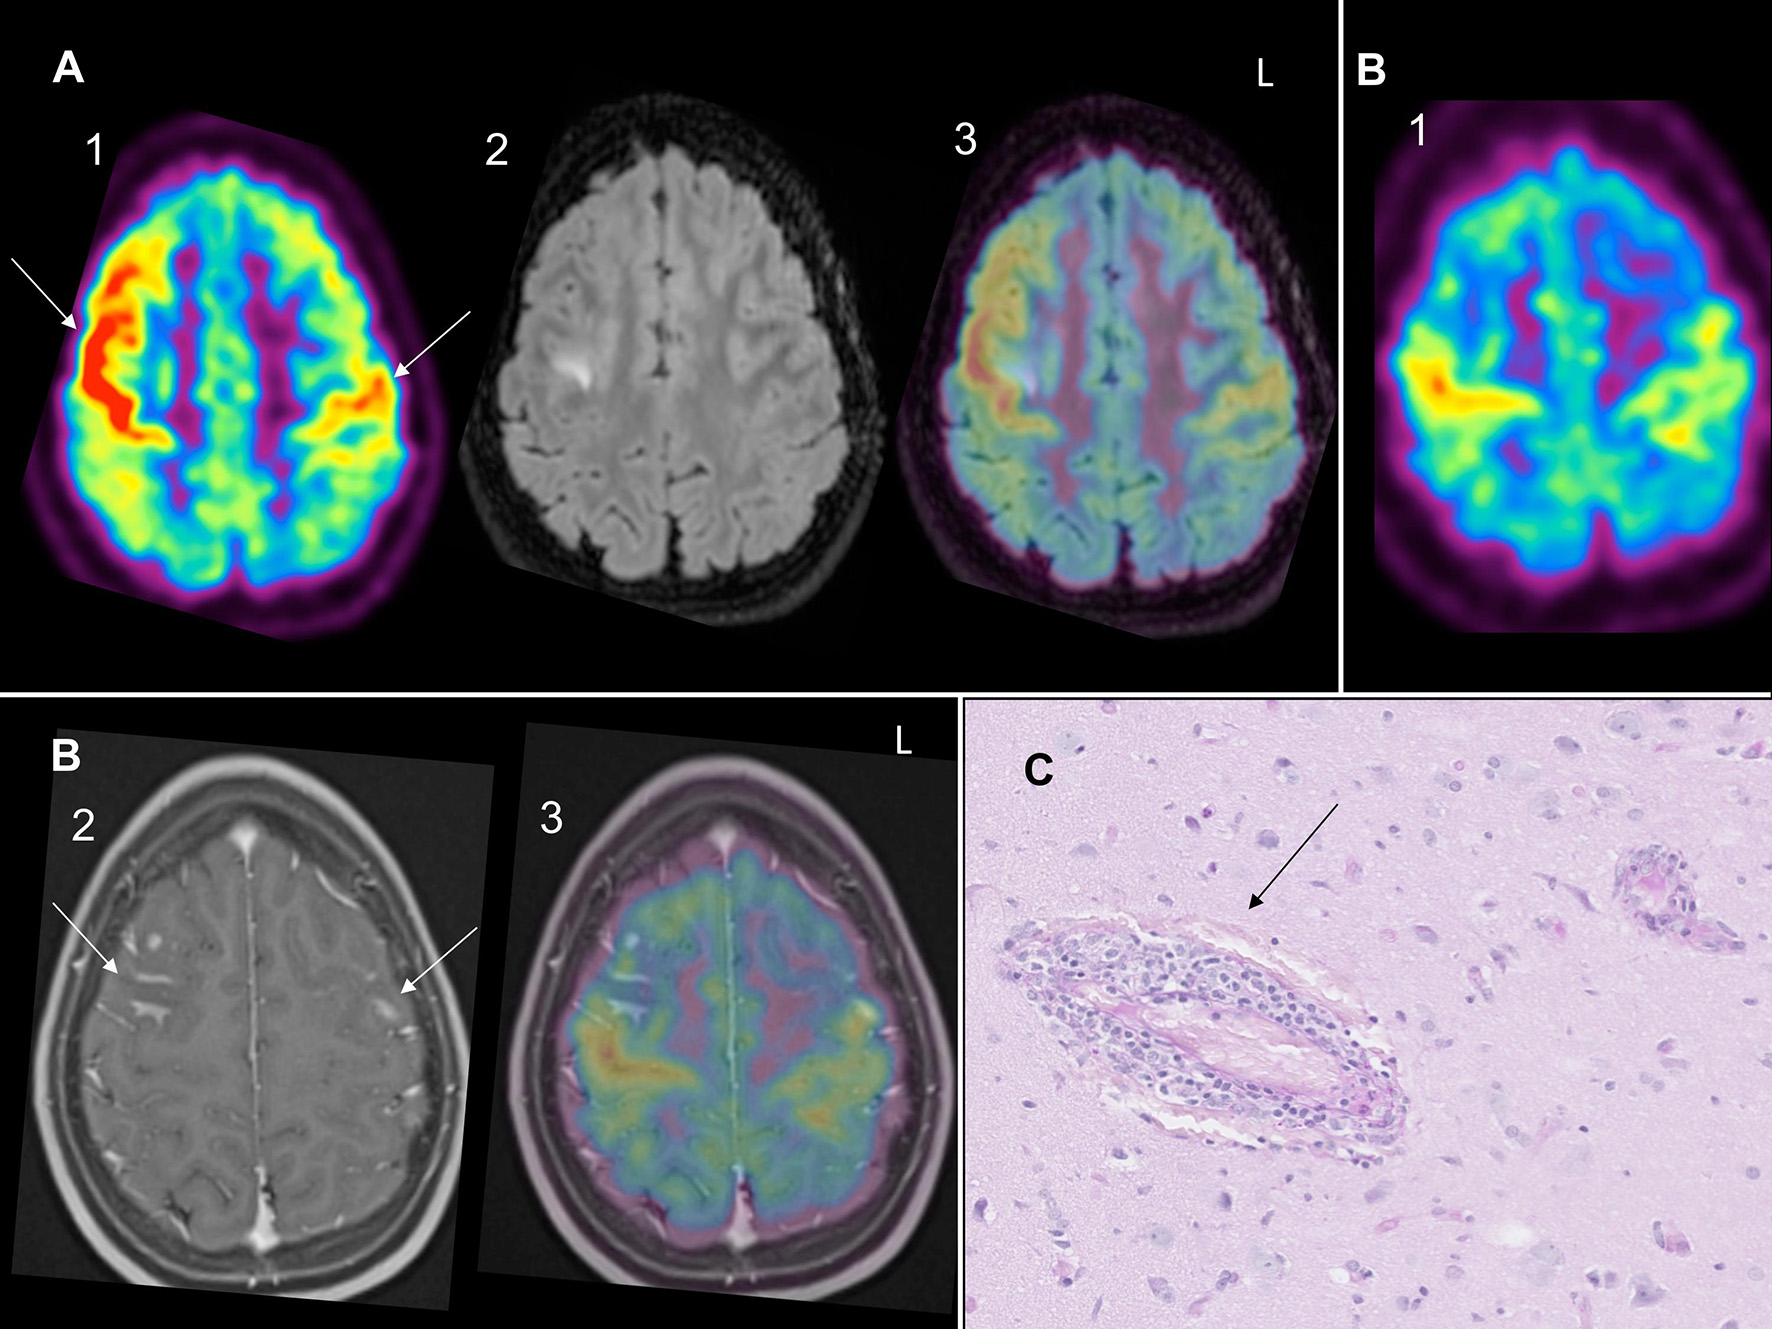

Patient 1 was a previously healthy 12-year-old girl, who presented an episode of loss of consciousness followed by transitory aphasia and paresthesia of the right upper limb suggestive of a focal seizure. In the emergency room, physical and neurological examination were unremarkable. The initial blood test and toxicological analysis were inconclusive. Conventional electroencephalogram (EEG) was normal and she was discharged with the scheduling of a brain MRI. Two days later, she presented a second episode associated with tonico-clonic movements of the right upper limb, deviation of the head and gaze to the right. On second admission, she also complained of chronic fatigue and recurrent headaches for 1 year. Blood tests showed an elevated sedimentation rate at 26 mm/h. The CSF revealed pleocytosis (16 leukocytes per μL, 80% lymphocytes). The extensive autoantibody search was negative, especially for anti-nuclear antibody (ANA), antineutrophil cytoplasmic antibody (ANCA), rheumatoid factor (RF) and anti-myelin oligodendrocyte glycoprotein (MOG). Brain MRI showed high signal intensities on T2-weighted imaging (-WI) and FLAIR images in the precentral sulcus bilaterally (Figure 1A) with enhancement on the T1-WI post-contrast images (Figure 1B) and vasogenic edema on diffusion-weighted images. EEG showed bilateral right>left frontal spike-waves. Whole body FDG-PET showed an increased right>left FDG-uptake in both frontal lobes (Figures 1A,B) and no extra CNS inflammation. PET-MR coregistration showed a mismatch between MRI and PET abnormalities (Figures 1A,B). We suspected svPACNS and we scheduled a brain biopsy to confirm the diagnosis. A few days later, she developed right eye pain, blurred vision and photophobia. The ophthalmological examination, which was normal on admission, showed bilateral papillary edema compatible with optic neuritis. This prompted us to perform a brain biopsy guided by MRI and FDG-PET with sampling of both MRI and PET abnormalities. The biopsy showed a lymphocytic predominant svPACNS (Figure 1C). She was treated with intravenous methylprednisolone pulse 30 mg/kg/d for 5 days followed by oral prednisone 2 mg/kg/d associated with levetiracetam 50 mg/kg/d and aspirin 5 mg/kg/d. Induction therapy also included a monthly dose of cyclophosphamide (600 mg/m2) for 7 months. Her symptoms progressively resolved and the antiepileptic treatment could be stopped. The ophthalmological examination was normal after 1 month of treatment, as well as the brain MRI in the middle of this first phase of treatment. The maintenance therapy included oral prednisone that was monthly tapered and mycophenolate mofetil daily (2 g/day) for one more year. The treatment was well-tolerated and she is currently in remission for 24 months under this regimen. A timeline with relevant data from the episode of care is represented in Figure 2.

Figure 1

(A) (1) Bilateral right> left (arrows) PET-FDG increased uptake in both frontal lobe cortices with (2) right FLAIR hypersignal and (3) PET-MR coregistration showing mismatch between PET hypermetabolism and FLAIR hypersignal. (B) (1) Bilateral right>left PET-FDG increased uptake in both frontal lobes with (2) bilateral (arrows) enhancement on T1 gadolinium and (3) PET-MR coregistration showing mismatch between PET hypermetabolism and T1 gadolinium enhancement. (C) Small vessels non-granulomatous lymphocytic svPACNS on Periodic Acid Schiff (PAS) coloration on histology (arrow).

No studies have searched to what extent there is a match between brain MRI signal abnormalities and areas of increased PET tracer uptake in svPACNS. Interestingly, in our two biopsy-proven svPACNS, we found an increased FDG uptake for Patient 1 and an increased MET uptake for Patient 2 in brain regions with but also without brain MRI abnormalities [see Figures 1A,B and Figure 1A in (6)]. This mismatch between brain MRI and PET is also evidenced in brain tumors as the metabolically active tumor burden extends considerably beyond the volume of MRI (5). As already mentioned, brain biopsy is the gold standard to confirm the diagnosis of svPACNS in order to evidence the perivascular lymphocytic infiltration. To ensure high diagnostic yield, this procedure needs to be “en bloc” incisional biopsy prior to electrocautery, with a volume of at least 1 cm3, containing leptomeninges, cortical gray matter and subcortical white matter (4). The diagnostic value of brain biopsy is also influenced by an adequate targeting of regions where brain inflammation is at the highest (4). Therefore, since our two cases demonstrate a mismatch between brain MRI and PET abnormalities, we suggest that using both imaging modalities to target brain biopsy, just as in brain tumors, might be an interesting strategy to increase the diagnostic yield of svPACNS. The strength of PET imaging in svPACNS lies in its association to brain biopsy. Limitations of PET include diagnosis delay due to limited availability, and the possible influence of previous immunosuppressive therapy on the findings, especially glucocorticoids that are often administrated in the early course of the disease. PET and brain biopsy should ideally be performed before initiating immunosuppressive treatment.